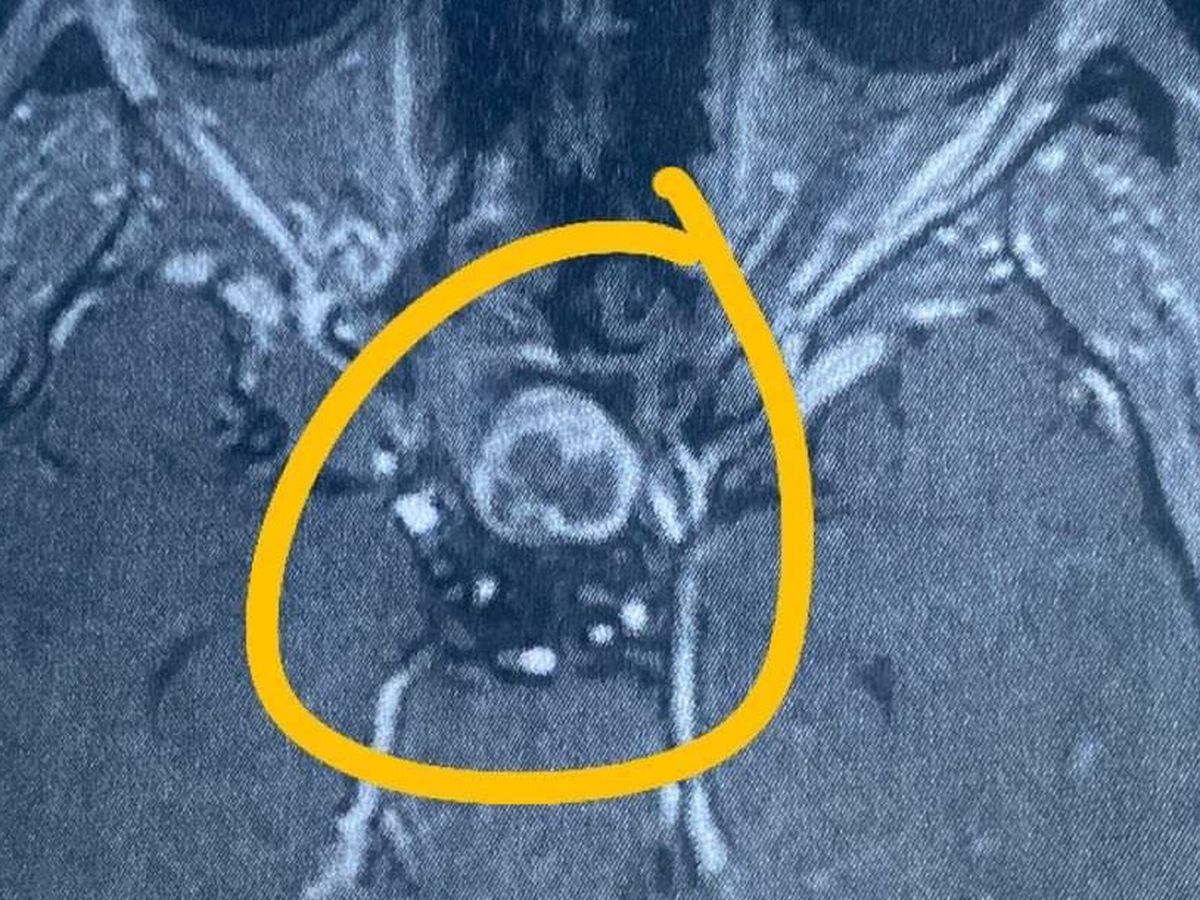

Hi, my name is Kristine and I'm doing fundraising for my upcoming surgery in the Philippines. I'm an international student here in Australia. But suddenly they found out that I have a pituitary tumor in my brain (pituitary macroadenoma).

The neurosurgeons doctor told me that I need to have surgery since I'm having bad headaches almost everyday and my vision is also affected.